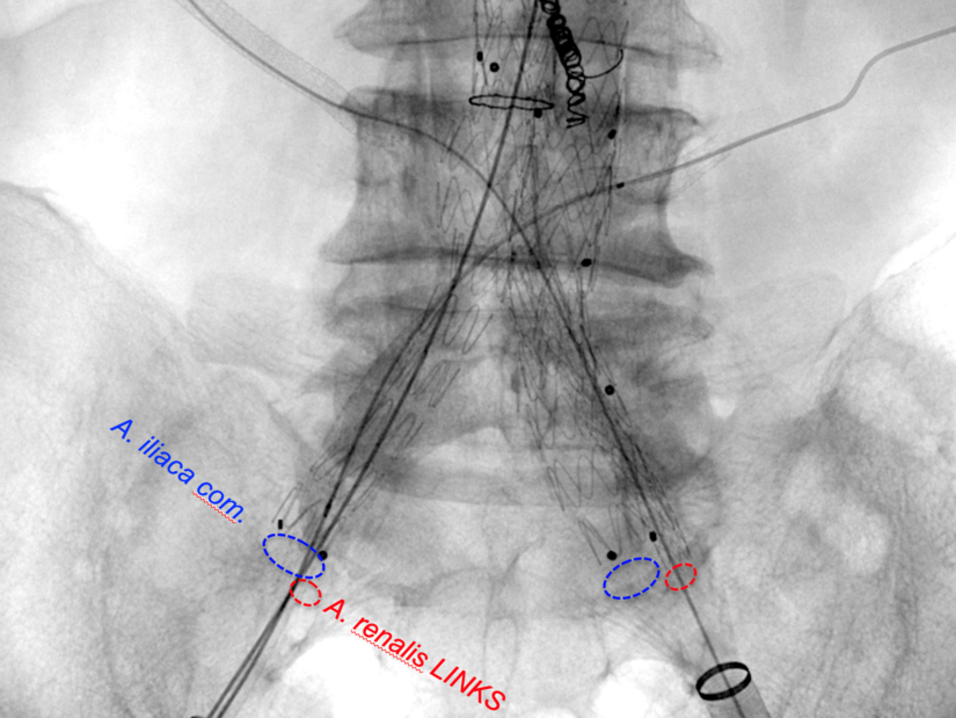

Auch eine atypische Versorgung zum Erhalt beispielsweise wichtiger zusätzlicher Nierenarterien zur Förderung der Nierenfunktion sind mit diesen Techniken umsetzbar.

Entsprechend unserem Anliegen, so viel wie möglich an vorhandenen Gefäßen zu erhalten, gelingt auch der Erhalt der Beckenarterien bei ausgedehnten aorto-iliakalen Aneurysmen mit diesen Techniken. Diese Gefäßversorgung bildet einen wichtigen Umgehungskreislauf bei arterieller Verschlusskrankheit zum Bein oder vaskulär bedingter erektiler Dysfunktion.

Bei einem nicht unerheblichen Anteil der Betroffenen sind keine Standard-Stentgraft-Materialien verwendbar, um eine sichere Abdichtung zu gewährleisten. In diesen Fällen kommen maßgefertigte Stentgraft-Prothesen zum Einsatz. Diese haben abhängig von der Lokalisation Verbindungen zu den übrigen wichtigen Baucharterien wie Nieren und Darm.